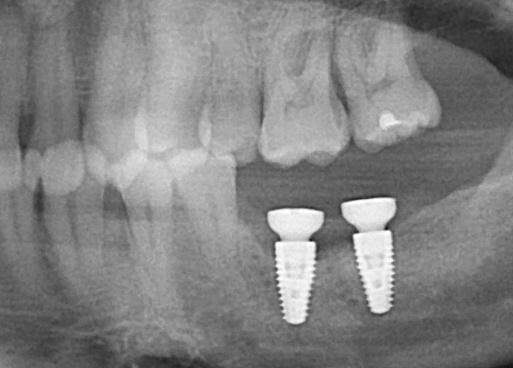

Most dental implants are engineered and delivered so they can be expected to provide many years of functional service to support replacement prosthetic teeth. There are numerous reasons and situations in which implant abutment or screw components fail by either fracturing from exposure to excessive forces or they become non-functional due to a changed clinical situation, or with time, have literally worn out. For these situations, Implant Mechanical Rescue (IMR) can aid in recovering these non-functional components from inside implants that are otherwise useful, so the implant can be used in an updated restorative treatment plan.

One of the most frustrating experiences for patients is having dental implant problems, which includes having a fractured implant, screw, or abutment removed. Although most dental implants are delivered successfully and function well for years, there are situations when an implant or restorative component can become compromised due to forces that cause a loose or fractured screw, connecting abutment, or failing restoration. Correction of these problems ranges from fairly simple to quite complex, requiring microscopic evaluation of compromised restorative components and rescuing with specialized instrumentation.

Dr Mastrovich’s practice is fully dedicated to, and focused on, implant mechanical rescue, which means he is able to retrieve broken abutment screws and abutments, with a high degree of clarity and ease. He does this through the use of a high-powered operative microscope (which most dentists do not have) to view inside the implant. The operating microscope enables Dr. Mastrovich to visualize inside the implant in a manner not necessarily visible with lower magnification. He then uses a combination of specially designed instruments to remove the fractured components, screws and abutments without further damaging the implant.